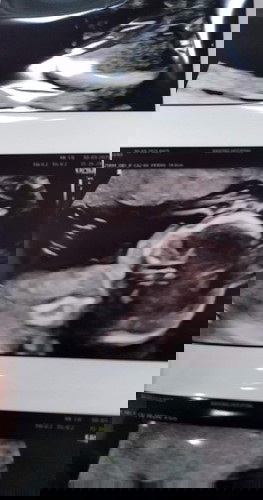

ซาวด์ เมื่อวาน อายุครรภ์ 19 Week เจอหินปูนเกาะที่หัวใจ อยู่ในกลุ่มเด็กดาวซินโดรม มันมาโอกาสหายไหมค่ะ แม่ๆคนไหน เจอเหมือนเราบ้าง 😔 เครียดมากเลยค่ะ